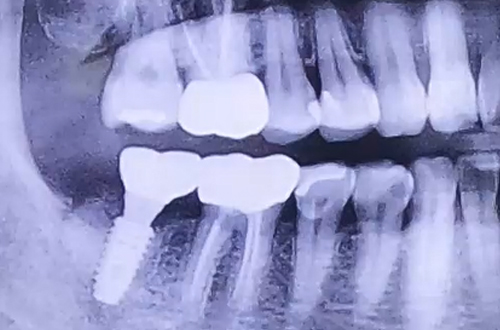

BEFORE

치아에 엄청난 통증을 호소하며 급하게 내원해주신 환자분이십니다.

살펴보니 이미 오래 전에 치료가 다 되었다고 생각했던 충치 치료를 했던 치아가 크게 쪼개진 상태였는데요.